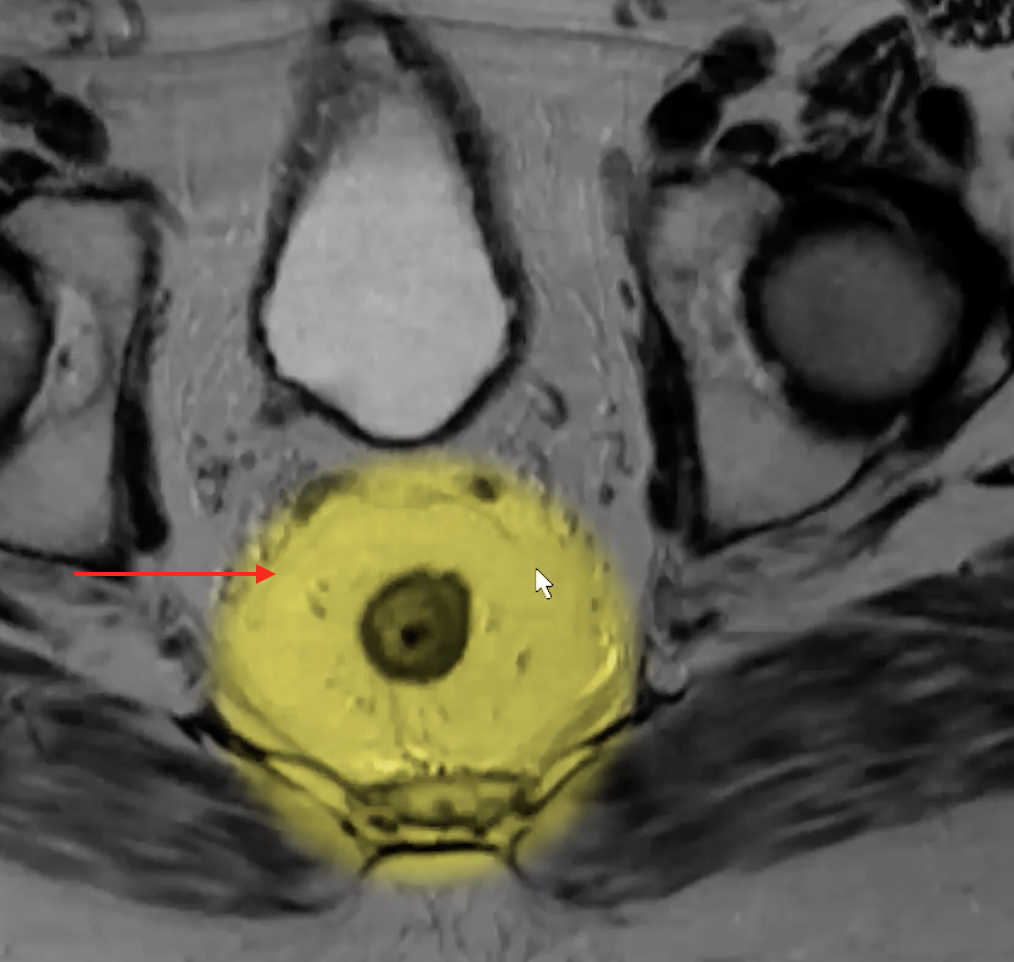

Mesorectal Fascia

• Thin dark line surrounding the mesorectal fat

• Like a tear drop shape

• Superiorly ends at the level of the recto-sigmoid junction where it blends into the sigmoid mesentery

• Inferiorly blends into the puborectalis and levator muscles

• Wide in the center